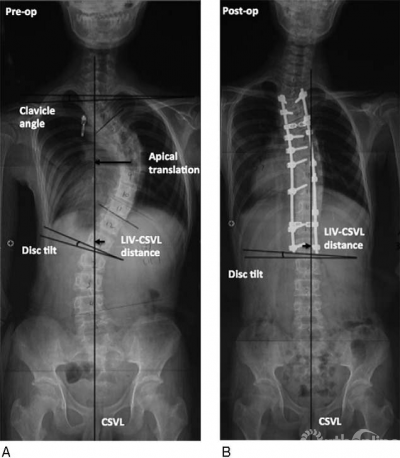

Wang等人[1]于2011年在Spine杂志上发表的文章中将远端附加现象定义为结构性主弯融合术后随访1年及以上时,主弯范围延长,最下固定椎(lowest instrumented vertebra,LIV)下方有更多椎体进入主弯,LIV以下第一个椎体偏离骶骨中垂线(center sacral vertical line,CSVL)5mm以上或LIV以下第一个椎间隙成角增加5°以上的现象。目前这一定义得到学界广泛的认可。远端附加现象多出现于行选择性胸弯融合的患者,主要是Lenke 1A型及Lenke 2A型AIS患者。其诊断标准为末次随访时,对比术后站立位脊柱全长正位片出现:

(1)主弯下端椎(lower end vertebra,LEV)向远端移动,主弯椎体数增加,LIV偏离CSVL 10mm以上;

(2)或是LIV以下第一个椎体偏离CSVL 5mm以上;

(3)或是LIV以下第1个椎间隙成角增加5°以上[1,2]。

Wang等人[2]回顾性分析45例Lenke 1A型AIS患者,其中23例(51%)矫形术后1年发生远端附加现象,统计学分析结果显示术前LIV远端第一个椎体(LIV+1)距离CSVL超过10mm为出现远端附加现象的独立危险因素,因此认为LIV应选择在偏移CSVL小于10mm的椎体头端第一个椎体。Matsumoto等[11]通过一项对112例Lenke 1A型AIS患者的多中心研究发现,未融合至最后触及椎(从骶骨向头端最后一个接触 CSVL 的椎体)为发生远端附加现象的独立危险因素,因此认为LIV应选择最后触及椎。

最后实质触及椎是LIV的最佳选择[8]

国内邱勇教授团队[12]回顾性分析104例Lenke 1A型AIS患者,其中23例(22.1%)发生远端附加现象,分析认为LIV的选择应位于最后实质触及椎(从骶骨往头端最后一个被CSVL平分的椎体)以降低远端附加现象发生率。此外,李明教授团队[13-15]的系列研究也认为选择最后实质触及椎作为LIV,术后发生远端附加现象的风险最低,同时应该考虑LIV距离CSVL不应超过1cm。因此,学界认为对于AIS患者行选择性胸弯融合手术的LIV应选择最后实质触及椎最为合适。